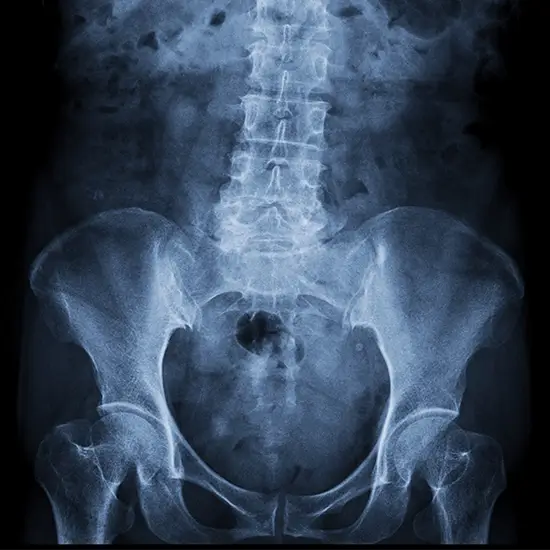

X-ray Right Hip AP View

The hip joint facilitates movement and supports body weight. In an Anterior-Posterior (AP) projection of the hip, X-rays are taken from the patient's front to their back. It shows any hip joint fractures, dislocations, bone lesions, or degenerative illnesses. There is discomfort in the groin, the side of the hip, the buttocks, and the knee.